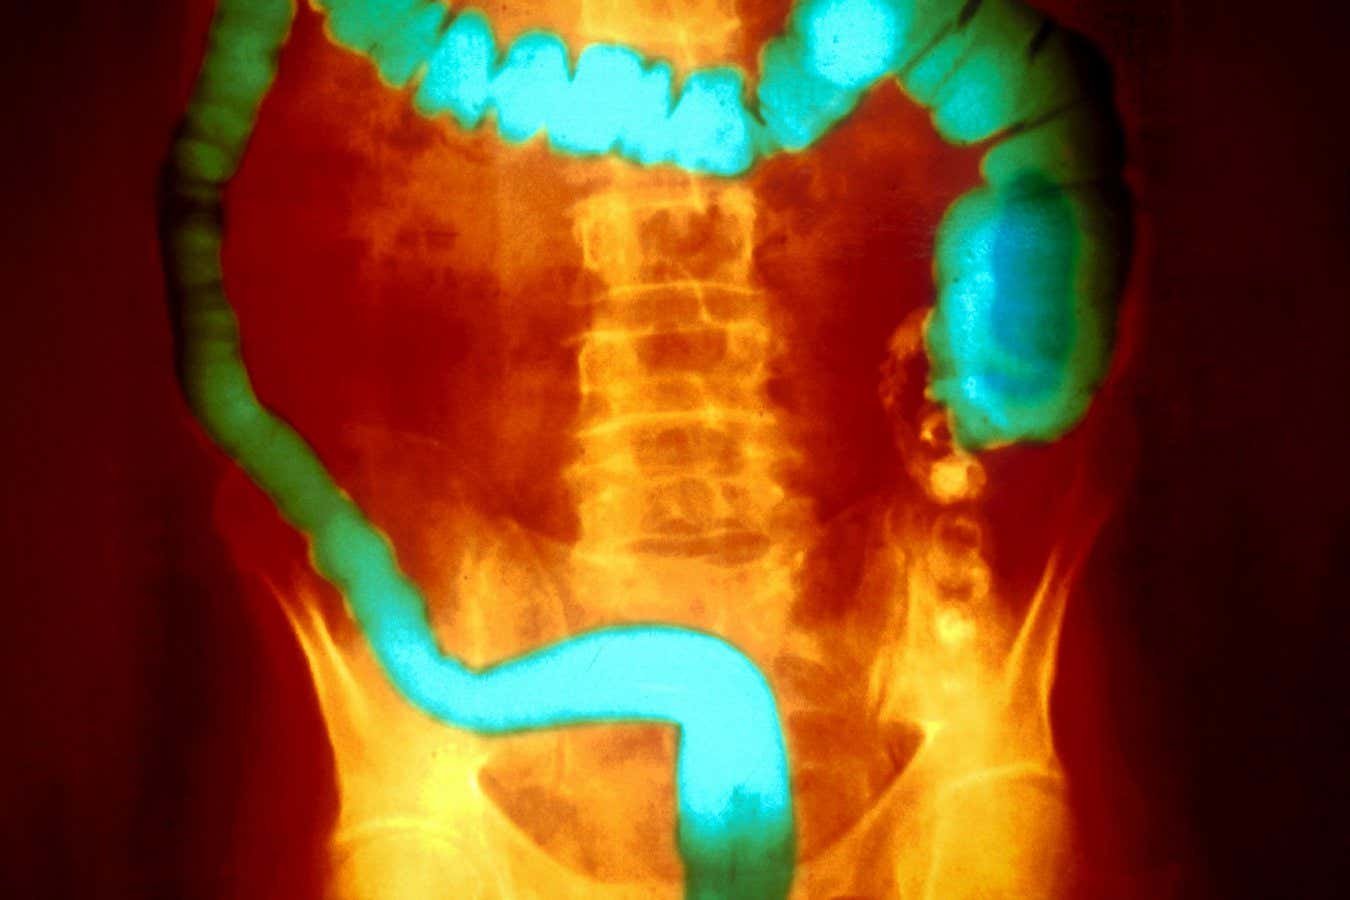

Ulcerative colitis is characterised by inflammation of the lining of the colon and rectum

Ulcerative colitis is one of the two main kinds of inflammatory bowel disease, or IBD. It is characterised by inflammation of the lining of the colon and rectum. People typically have periods of no symptoms that alternate with flare-ups. The most serious cases can require the removal of the colon.